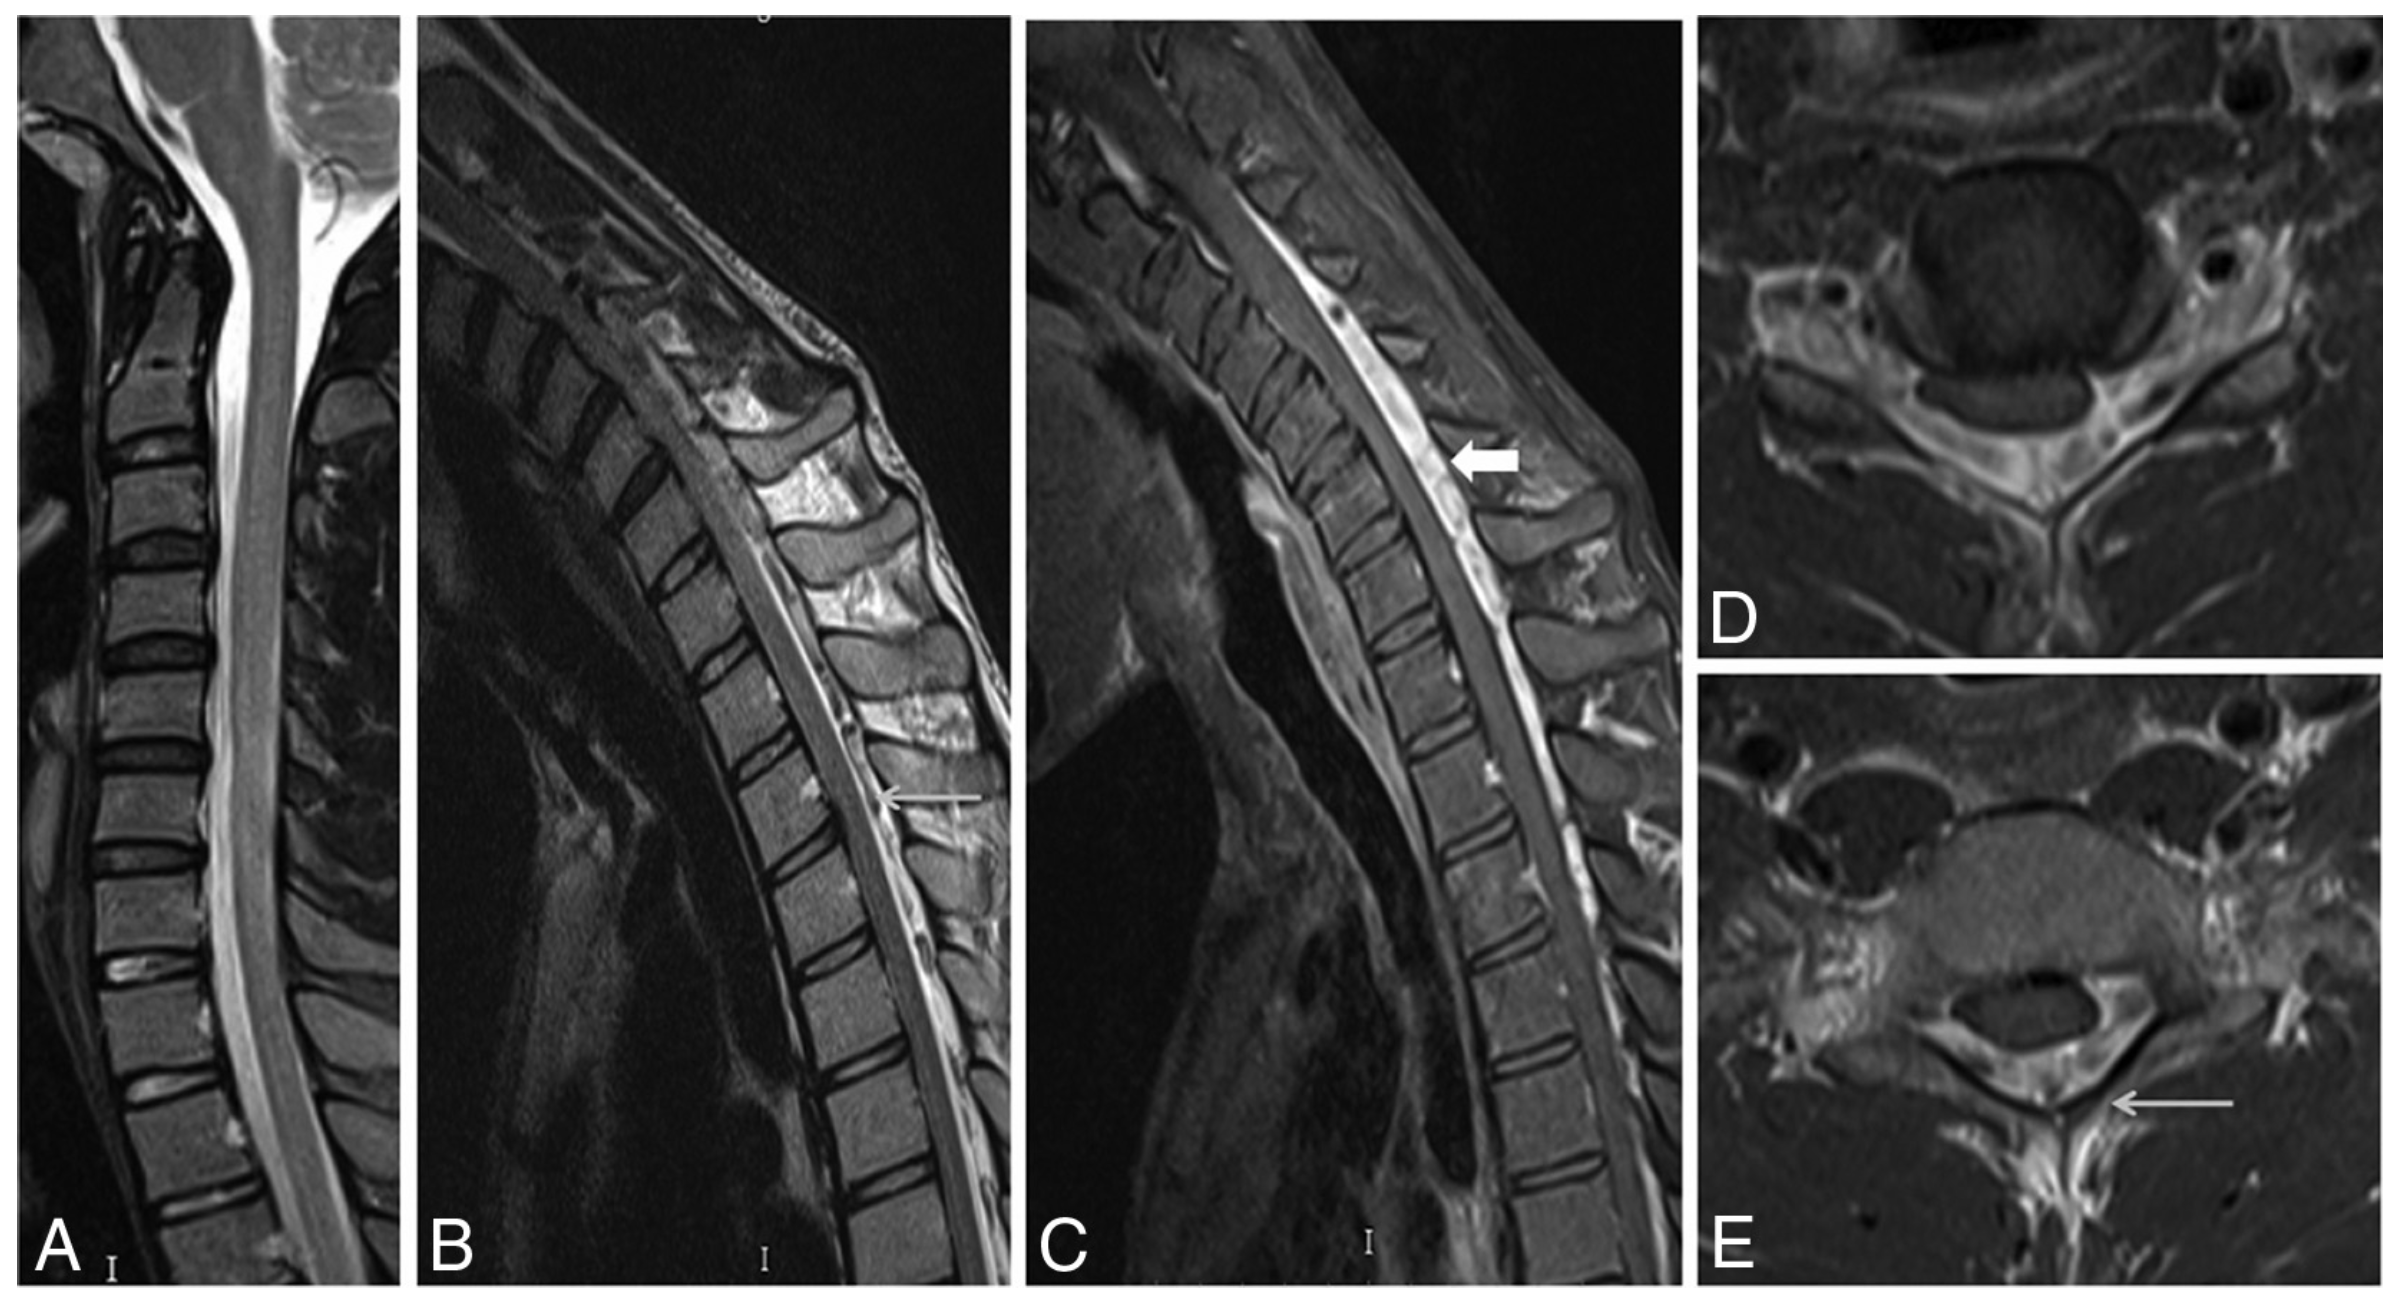

Results

Imaging findings

fig 2

figs. 4, 5, 6